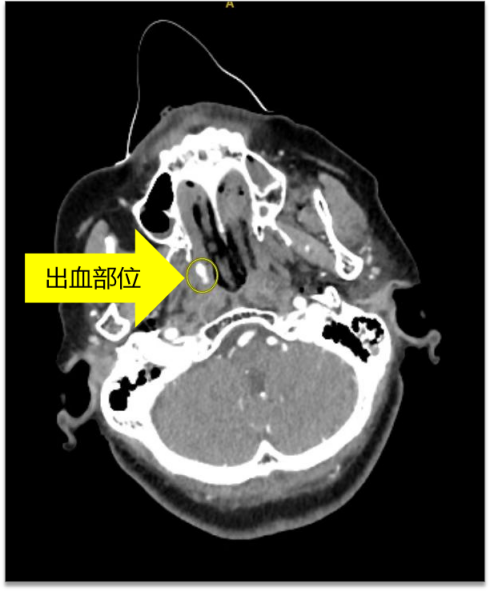

结合头面部增强CT检查

判断为面部骨折导致的血管破裂

进而引起大出血

若不及时止血,随时会危机生命